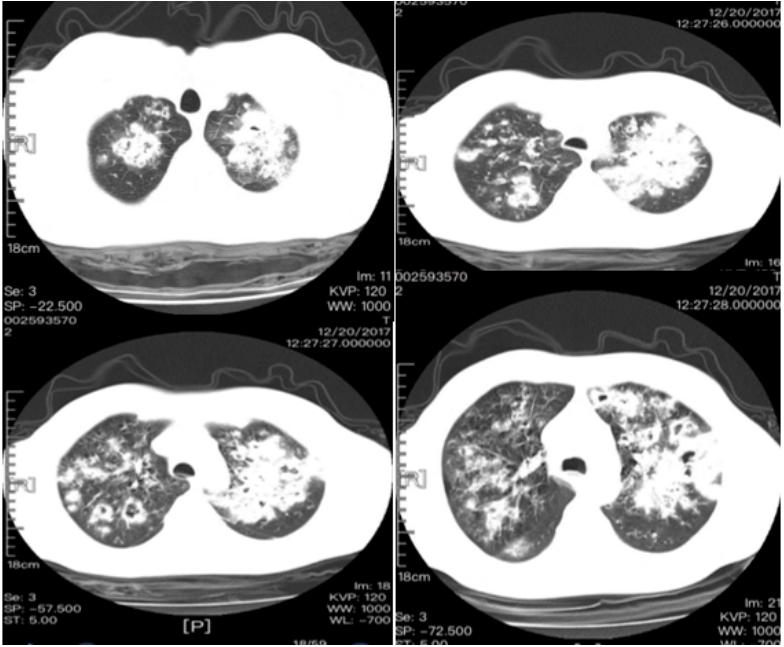

注:CDC和NIH对于新冠背景下免疫低下人群的定义:癌症治疗人群、实体器官移植受者、原发性免疫缺陷、晚期或未经治疗的HIV感染者或长期使用高剂量糖皮质激素(>20 mg /d)和抑制免疫系统的其他药物(CNI,抗代谢物,生物制剂)。重症COVID-19患者纤支镜下发现支气管黏膜斑片状伪膜或溃疡病变提示CAPA可能。侵袭性曲霉病细支气管炎(IATB)是COVID-19患者罹患侵袭性曲霉病(IA)的重要临床表现之一,在IAPA和CAPA患者中的比率分别为55%和10%~20%,后者的发病率较低,可能与临床医师对此类患者进行气管镜操作的意愿低有关。IAPA和CAPA疾病定义的专家共识中均将气管镜发现的气道病变纳入到细支气管炎型IAPA和CAPA患者的诊断中,具体镜下表现包括:斑片状伪膜或溃疡病灶的形成。在一项COVID-19合并曲霉细支气管炎的队列研究中,图8A为COVID-19伴曲霉细支气管炎患者气管镜下见溃疡和黄白色斑片伪膜形成(箭头);图8B为COVID-19伴曲霉细支气管炎患者尸检中见因黏膜侵袭和溃烂所致支气管软管暴露(箭头);图8C为COVID-19伴ARDS患者气道组织标本中菌丝对细支气管黏膜的侵袭。图8 COVID-19伴曲霉细支气管炎患者支气管镜和病理所见图源:Eur Respir J, 2022, ;59(5):2103142.图9为上海瑞金医院RICU收治的一例流感病毒感染继发侵袭性肺曲霉病(IPA)患者, 从影像学中可以看到病变非常严重, 沿支气管分布, 非常密集, 以及多发空洞坏死(图9)。该患者最终死亡。可见混合感染会给患者带来非常大的危害。

图9 流感病毒感染继发IPA患者的影像学